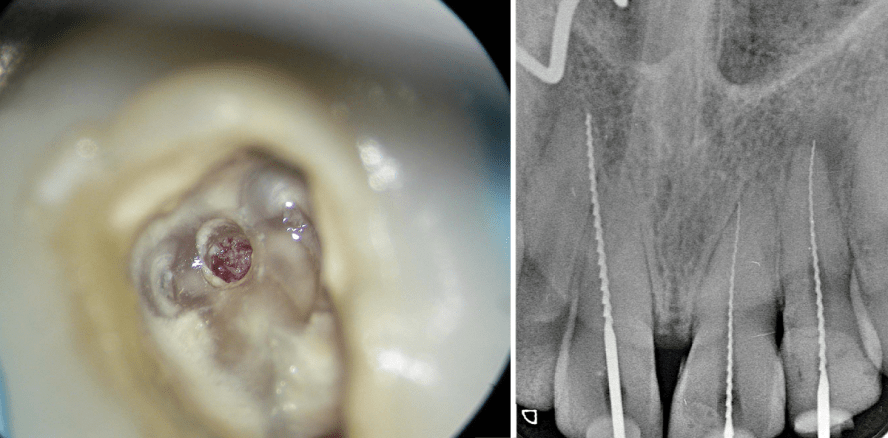

Die Schaffung einer optimal platzierten und an die Pulpaanatomie in Form und Umfang angepassten endodontischen Zugangskavität ist ein entscheidender Schritt im Hinblick auf ein optimales

Behandlungsergebnis und die Prognose einer endodontischen Behandlung.1,2 Der folgende Beitrag soll auf mögliche Schwierigkeiten bei Trepanation, Auffinden und Darstellung aller Wurzelkanalsysteme hinweisen, für anatomische Variationen sensibilisieren sowie instrumentelle und praktische Lösungsansätze zur Schaffung einer strukturschonenden endodontischen Zugangskavität aufzeigen.

• der Achsrichtung des Zahnes (Abb. 1 und 2).

Bei der Verifizierung dieser einzelnen Parameter sind zweidimensionale, ggf. exzentrische Röntgenaufnahmen hilfreich. Beim Verdacht auf zweidimensional nicht darstellbare anatomische Variabilitäten wie beispielsweise Radix entomolaris, c-förmige Wurzelanatomien oder Vorliegen interner oder externer Wurzelresorptionen, Invaginationen oder Dentikeln hilft die Anfertigung einer Digitalen Volumentomografie bei der Planung des korrekten Zugangs zum Pulpakavum und den Wurzelkanalsystemen.3,4

Die substanzschonende, strukturerhaltende Präparation der endodontischen Zugangskavität wird durch Zuhilfenahme von optischen Vergrößerungshilfen wie Lupenbrille, Dentalmikroskop oder Kamerasystemen erleichtert, in schwierigen Fällen dadurch erst möglich.5 Komplikationen bei nicht korrektem Zugang wie Via falsa bis hin zur Perforation im Bereich der klinischen Krone oder der Wurzel sowie Schwächung der Restzahnsubstanz durch zu großen Abtrag von Zahnhartsubstanz können durch gute koaxiale Ausleuchtung in Kombination mit ausreichender Vergrößerung vermieden werden (Abb. 3–9). Je substanzschonender die Zugangskavität angelegt wird, desto niedriger ist das Risiko für das spätere

Auftreten von Längsfrakturen des endodontisch behandelten Zahnes.